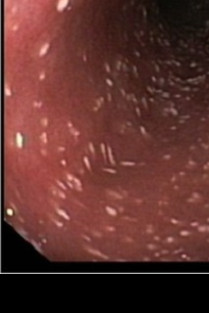

Vous souhaitez approfondir vos connaissances sur les dernières avancées en gastroentérologie féline ? Participez à notre formation "Actualités en gastroentérologie féline" et découvrez les innovations, les nouvelles recherches et les meilleures pratiques du domaine.

Cette formation vous permettra de mieux diagnostiquer et traiter les troubles gastro-intestinaux chez les chats, tout en vous tenant informé des protocoles les plus récents. Retrouvez des cas cliniques concrets et des échanges enrichissants avec le DV Amandine Drut, spécialiste en médecine interne. Ne manquez pas cette occasion de renforcer vos compétences et d'améliorer le bien-être de vos patients félins !

- Maîtriser la démarche diagnostique générale lors de troubles digestifs chroniques (diarrhée, vomissements, baisse d'appétit, perte de poids) .

- Savoir comment différencier une maladie inflammatoire chronique intestinale d'un lymphome de bas grade.

- Savoir reconnaître une forme digestive de PIF.

- Mettre à jour ses connaissances sur la fibroplasie sclérosante éosinophilique.

- Connaître les particularités de l'insuffisance pancréatique chez le chat.